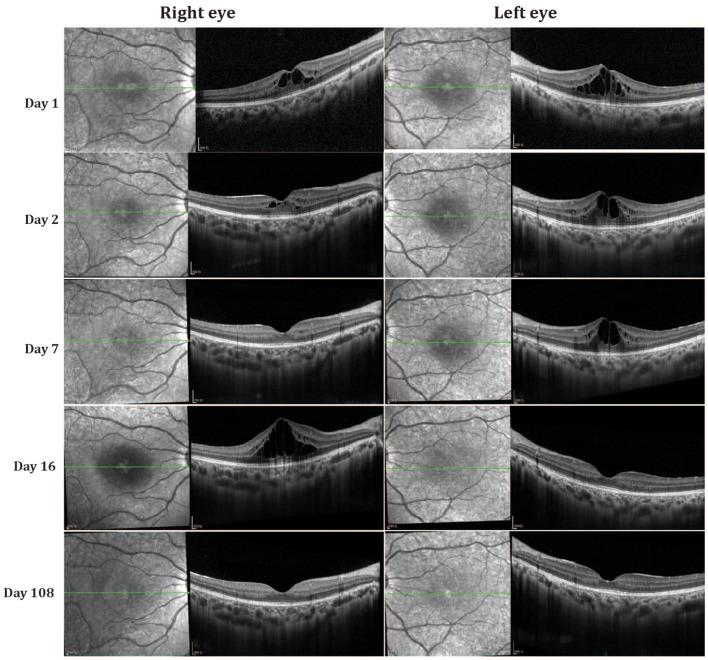

Cystoid macular edema (CME) is a common complication in various retinal disorders, often leading to significant central vision impairment. However, the underlying genetic causes and detailed clinical features in patients with fluctuating CME remain unclear. This retrospective, observational case series analyzed two patients from a single family with fluctuating CME, focusing on both clinical and genetic aspects. Data were collected and analyzed from September 2022 to January 2023 at a single center. Comprehensive ocular examinations, including best-corrected visual acuity tests, color fundus photography, fundus fluorescein angiography (FFA), optical coherence tomography (OCT), visual field tests, flash electroretinography, multifocal electroretinography, and electrooculography, were performed. Genetic analysis was conducted using whole exome sequencing, with confirmation through Sanger sequencing and co-segregation analysis. The results identified two compound heterozygous variants in the gene: c.562C>G p.Q188E and c.5929C>T p.R1977W in both patients. Fundus fluorescein angiography revealed cystoid hyperfluorescence in a petaloid pattern in the foveal area and a honeycomb pattern parafoveally. OCT showed that macular cystoid changes were primarily located in the outer nuclear layer (ONL), and full-field electroretinography indicated rod-cone dysfunction. Over a 108-day follow-up period, CME in both patients exhibited fluctuating changes without any treatment. This case series suggests that the identified MYO7A variants are likely associated with fluctuating CME, expanding the phenotypic spectrum of MYO7A and providing new insights into the mechanisms underlying CME. Identifying these MYO7A variants bridges genetic research with clinical diagnostics, potentially offering more precise and personalized treatment strategies for retinal disorders.

黄斑囊样水肿(CME)是各种视网膜疾病中的常见并发症,常导致严重的中心视力损害。然而,波动性CME患者的潜在遗传原因和详细临床特征仍不清楚。本回顾性观察性病例系列分析了来自一个家族的两名波动性CME患者,重点关注临床和遗传方面。2022年9月至2023年1月在单一中心收集并分析数据。进行了全面的眼部检查,包括最佳矫正视力测试、彩色眼底照相、眼底荧光血管造影(FFA)、光学相干断层扫描(OCT)、视野测试、闪光视网膜电图、多焦视网膜电图和眼电图。使用全外显子组测序进行基因分析,并通过桑格测序和共分离分析进行确认。结果在两名患者的 基因中鉴定出两个复合杂合变异:c.562C>G p.Q188E和c.5929C>T p.R1977W。眼底荧光血管造影显示黄斑区呈花瓣样囊样高荧光,黄斑旁呈蜂窝样。OCT显示黄斑囊样改变主要位于外核层(ONL),全视野视网膜电图显示视杆 - 视锥功能障碍。在108天的随访期内,两名患者的CME在未接受任何治疗的情况下均表现出波动变化。该病例系列表明,鉴定出的MYO7A变异可能与波动性CME相关,扩展了MYO7A的表型谱,并为CME的潜在机制提供了新见解。鉴定这些MYO7A变异将基因研究与临床诊断联系起来,可能为视网膜疾病提供更精确和个性化的治疗策略。